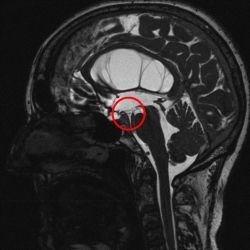

Prinzipiell stehen bei noch offener Fontanelle die Sonographie und die Kernspintomographie (MRT) zur Verfügung. Die Sonographie hat meist eine zu geringe Auflösung um zur Ursachendiagnostik eingesetzt zu werden. Die Computertomographie ist zur Ursachendiagnostik nicht sinnvoll, da der Informationsgehalt zu gering und die Strahlenbelastung für das kindliche Gehirn problematisch ist und vermieden werden soll. Somit ist die MRT die Untersuchung der Wahl. Da die diagnostische Präzision des MRT im Wesentlichen von der Qualität der Untersuchung abhängt, führen wir eine speziell auf die HIrnwasserräume abgestimmte hochauflösende Kernspintomographie, ggf. in Narkose, durch. Die Qualität dieser Aufnahmen unterscheidet sich erheblich von einer sog. „Standard-Kernspintomographie“. Mit diesem Vorgehen gelingt es häufig, zumindest eine erkennbare Ursache für einen Hydrocephalus darzustellen.

Eine angeborene Erweiterung der Hirnkammern kann bedingt sein durch einen Verschluss/Verengung der natürlichen inneren Hirnwasserwege, z.B. im Bereich des sog. Wasserganges (Aquädukt) oder im Bereich der Ausflussöffnungen aus der 4. Hirnkammer in die äußeren Hirnwasserräume. Dies kann sowohl bei einer isolierten Fehlbildung z.B. des Aquädukts der Fall sein, aber auch im Rahmen von komplexeren Fehlbildungen des Gehirns oder des Rückens (Spina bifida) auftreten. Eine andere Ursache ist eine Blutung in die Hirnkammern während der Schwangerschaft, die nachfolgend zur Verklebung der Hirnwasserwege führt. Bei manchen Fehlbildungsformen ist eine klare Ursache für den Hydrocephalus nicht zu erkennen. Man muss davon ausgehen, dass selbst hochauflösende MRT-Diagnostik (s. unten) bestenfalls einen Teil der möglichen zugrunde liegenden Ursachen für die Ausbildung eines Hydrocephalus anzeigt.

Ist die einzige Ursache des Hydrocephalus eine erworbene, umschriebene Abflussbehinderung des Hirnwassers im Bereich des sog. Aquädukt, der 4. Hirnkammer oder der Ausflussöffnung aus der 4. Hirnkammer, so kann diese Abflussbehinderung durch eine „innere Umleitung“ durch Eröffnung des Bodens des 3. Ventrikels umgangen werden.

Das hierfür verwendete Verfahren ist die endoskopische Ventrikulozisternostomie (englisch endoscopic third ventriculostomy = ETV). Hierbei wird ein feines Endoskop in die erweiterten Hirnkammern vorgeschoben und damit am Boden des 3. Ventrikels in einem Areal, welches keine Funktion enthält, unter Sicht meist mit einem Speziallaser eine Öffnung geschaffen.